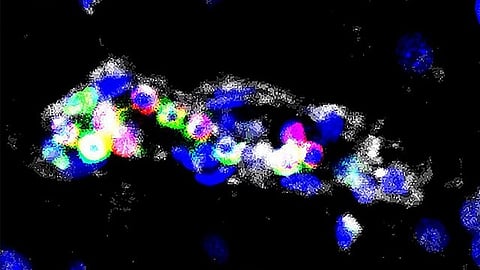

When proliferation is no longer properly regulated, this can lead to the development of various diseases, among which cancers represent the most striking example. In a study published in Nature Immunology, Professor Thomas Marichal (Professor at ULiège, Welbio investigator at the WEL Research Institute) and his team from the GIGA Institute at ULiège discovered that this ability to proliferate is not merely restricted to stem cells, but is also an as-yet-unknown function of blood immune cells, the monocytes. Indeed, blood monocytes, previously considered as differentiated cells, are capable of proliferating and generating a pool of monocytes in the tissues in order to give rise to macrophages, which are important immune cells that protect us against microbes and support the proper functioning of our organs.